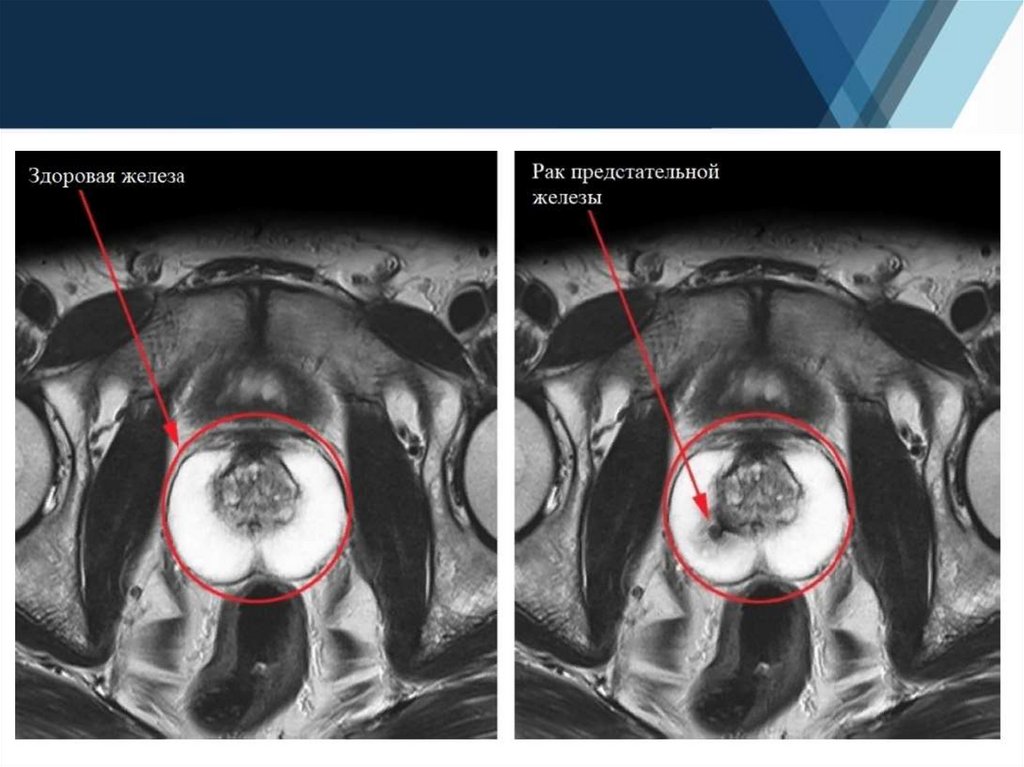

3. Исследование внутренних половых органов у мужчин (предстательная

железа, семенные пузырьки):

- диагностика воспалительных заболеваний;

- диагностика доброкачественной гиперплазии предстательной железы;

- дифференциальная диагностика злокачественных и доброкачественных опухолей;

- оценка распространенности злокачественного опухолевого процесса;

- изучение метаболизма предстательной железы на биохимическом уровне

(водородная МР-спектроскопия).